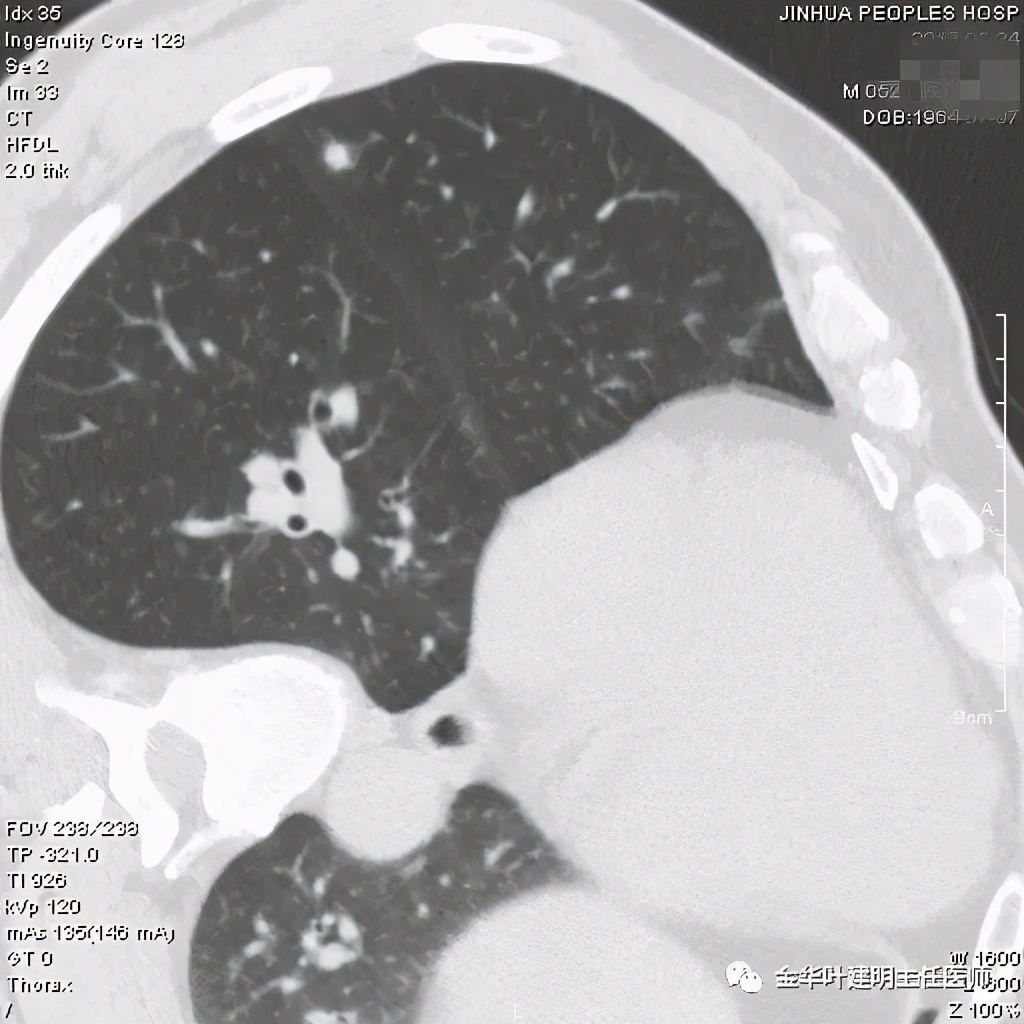

患者为48岁男性,检查发现左肺上叶实性结节,临床没有炎症表现,肿瘤指标不高,没有查过结核及隐球菌荚膜抗原试验或G试验、M试验等。我们先来看其前一个月时的平扫影像:

我们见左上实性病灶,主病灶旁有卫星灶,有血管进入,但也有贴边走行,边缘略显模糊,膨胀感与细毛刺不明显,收缩力也不明显。下面是其靶扫描的片子:

病灶实性,但收缩力弱,绿色箭头示病灶边缘有一圈晕征(模糊且均匀)

病灶实性,但收缩力弱,没有细毛刺征,实性部分比较圆润,绿色箭头示病灶边缘有一圈晕征(模糊且均匀)

此层面红色箭头示有卫星灶,粉色箭头示主病灶

红色示卫星灶,粉色示病灶,绿色示边缘晕征

此层面相对最不舒服,病灶表面不平整。桔色箭头示血管进入病灶,但仍有绿色箭头示病灶有晕征(边缘是模糊的,不似肿瘤那种细毛刺且相对清楚轮廓)

紫色箭头示病灶的边缘向内凹陷,说明无膨胀性,绿色示晕征,粉色箭头指向病灶

此层面示病灶呈三角形,缺乏膨胀性,边缘较直,没有毛刺征,实性部分没有收缩纠集感,绿色箭头示晕征